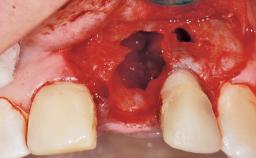

A 30-year-old female patient had lost tooth 21 and was referred to our clinic for consultation and treatment. Due to advanced apical infection, tooth 21 had been extracted two months earlier at another clinic and an acrylic-resin tooth had been bonded to the adjacent teeth. The patient desired implant treatment to avoid any damage to the adjacent natural teeth. While the patient had no history of any systemic disorder, she was a heavy smoker and exhibited medium to advanced periodontitis in the entire jaw. After the initial treatment to achieve a pocket probing depth of less than 4 mm and no bleeding on probing, a decrease in the height of the papillae mesial and distal to the extraction site and overall gingival recession were observed.

| Bone Augmentation | Horizontal|Staged |

| Augmentation Materials | Autogenous chips|Membrane |